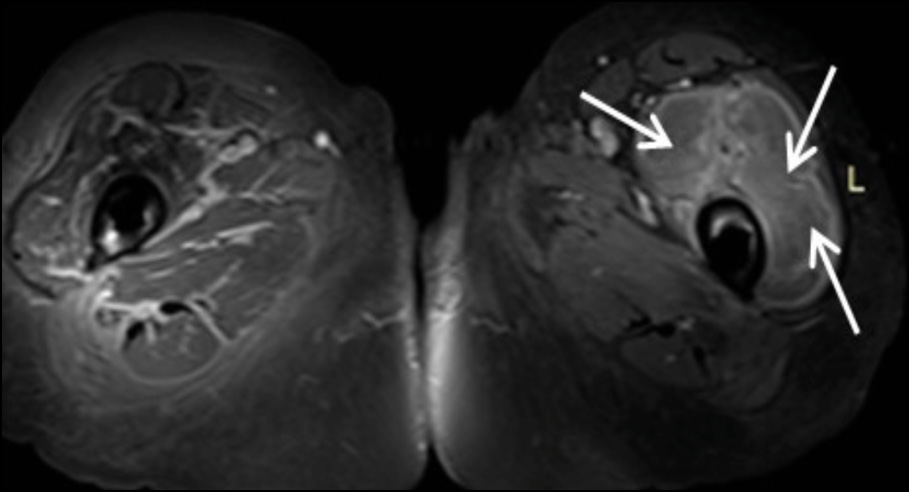

The chest X-ray was normal, with no hilar lymphadenopathy observed. Standard hip radiography was satisfactory and did not show any obvious alterations around the implant (Figure 1). The patient’s white blood cell count was 17.2×109/L with a neutrophilia (14.2 × 109/l), C-reactive protein (CRP) of 20mg/l (<0.5 mg/l), thrombocytopenia, elevated fibrinogen (478 mg/dl), and elevated high-sensitive troponin (1893 ng/dl), which was attributed to Type II ischemia, which further refers to a form of ischemia associated conditions that cause an imbalance between myocardial oxygen supply and demand. The patient was initially administered piperacillin - tazobactam and daptomycin intravenously (i.v). Due to persistent pain which extended above the knee the next days, the patient underwent Magnetic Resonance Imaging (MRI) (Figure 2a-e). MRI showed large encapsulated multilobular fluid collection with internal septa adjacent to the endoprosthesis of the left hip joint (Figure 2a-2b). This collection extended anteriorly beneath the deep fascia, causing displacement of the quadriceps muscle and protruding into the iliopsoas pouch. Its maximum outer diameter measured 12 cm.

The collection exhibited heterogeneous content, peripheral enhancement, as well as solid-enhancing wall components (Figure 2c-2d). Moreover, bilateral myositis was noted in the upper thigh muscle groups, with abscess formation in the left rectus femoris and the left vastus lateralis (Figure 2e). These findings suggested the presence of an inflammatory pseudotumor following hip arthroplasty, possibly compounded by systemic bacteremia, as evidenced by a history of cat bite. Fluid accumulation was also evident in the pelvic cavity.

Figure 2c - Coronal T1 post Gd Fat –Suppression image at the level of pubic bone. White arrow shows the peripheral enhancement of the encapsulated collection.

Figure 2d - Axial T1 post Gd Fat –Suppression image at the level of femoral neck. White arrow shows the peripheral enhancement of the encapsulated collection.

Figure 2e - Axial T1 post Gd Fat –Suppression image at the level of proximal femur. White arrow shows abscess formation in the left rectus femoris and the vastus laterali.